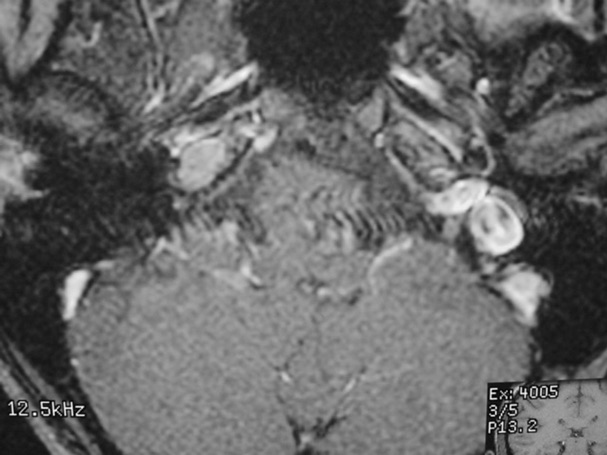

The petrous apex is a relatively inaccessible area that can occasionally harbor serious disease. Disease processes that usually cause symptoms are typically inflammatory or neoplastic in nature. Petrous apex lesions typically cause nonspecific symptoms such as headache, but as the lesion becomes more extensive, adjacent structures such as cranial nerves can become involved. A common early and specific sign of a petrous apex process is abducens palsy. Current imaging techniques can usually provide enough supplemental information to allow a focused plan of treatment. It is important to determine whether a petrous apex lesion can be observed or, if surgical treatment is required, whether a drainage or excision is required. There are various available surgical approaches to the petrous apex. The choice depends on the status of hearing function as well as the suspected pathology, which will dictate whether a drainage or excisional procedure is required.

- Summarize the types of pathology that can occur in the petrous apex, the imaging required, and proper interpretation of information so that a proper differential diagnosis can be formulated.